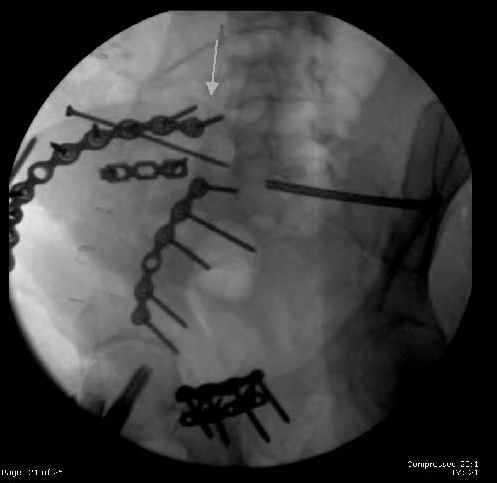

The mal-alignment that you indicated by the arrow in your photo of the ilium, do you have some idea as to how that occurred? was the crescent component locked in such a manner that it could not be moved?

So, there I was with the aforementioned info on my mind, and my R iliac wing was a little malreduced. I think it's in residual extension and some external rotation, explaining the 5-6mm gap/step

on the posterior R iliac wing. (When I loooked at the inlet fluoro, the L obturator foramen was more visible than the R obt foramen, as was the R ischial spine) so it's not as stable as if it were

anatomic, despite all the metal. This came from hesitance to take down all the posterior paraspinals to really see the R posterior crest (where the malreduction is best seen on the iliac oblique view), and I could see the entire iliac fossa and most of the crest anyway.